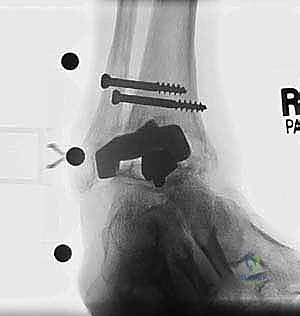

* دمج الكاحل (Ankle Arthrodesis): إذا كان التآكل العظمي هائلاً ولا يسمح بتركيب مفصل جديد، يتم إزالة المفصل الصناعي ودمج عظمة الساق مع عظمة الكاحل باستخدام مسامير وصفائح معدنية وطعوم عظمية.

من أعقد التحديات التي تواجه جراحي العظام هي حدوث كسور في الكعب الداخلي (Medial Malleolus) أو الخارجي (Lateral Malleolus) في وجود مفصل صناعي. تحدث هذه الكسور لعدة أسباب:

1. ترقق العظام: حول المفصل الصناعي نتيجة لعدم استخدام الطرف بشكل طبيعي (Stress Shielding).

2. الاصطدام الميكانيكي (Impingement): إذا كان حجم المفصل الصناعي أكبر من اللازم، فقد يضغط على الكعبين من الداخل ويؤدي لكسرهما بمرور الوقت.

3. الإصابات المباشرة: مثل السقوط أو التواء الكاحل.

علاج هذه الكسور يتطلب مهارة فائقة من الدكتور محمد هطيف، حيث يتم استخدام تقنيات الجراحة الميكروسكوبية وتثبيت الكسور باستخدام صفائح معدنية دقيقة ومسامير (Locking Plates) دون المساس بثبات المفصل الصناعي، أو يتم دمج علاج الكسر ضمن عملية مراجعة المفصل الكلية إذا كان المفصل نفسه تالفاً.